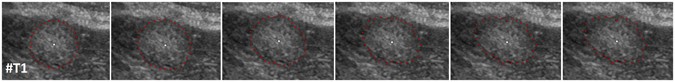

The segmentation approach of this study belongs to the class of graph-based algorithms28. Graph-based methods convert an image or parts of it into a graph G(V, E) that consists of nodes n ∈ V and edges e ∈ E. The nodes n ∈ V are sampled in the image, except for two virtual nodes s ∈ V and t ∈ V, which are called the source and the sink, respectively. The two virtual nodes are used to calculate an s-t-cut25 after the graph construction and divide the graph into two parts: the foreground (e.g., the liver metastasis) and the background (e.g., the surrounding liver tissue). Furthermore, the edges e ∈ E establish connections between the (virtual) nodes (for example, the edge \(\langle {v}_{i},{v}_{j}\rangle \in E\) connects the nodes v i , v j 29). However, the first step of our approach is to sample the graphs’ nodes along radial rays that are equidistantly distributed around a fixed point in a clockwise manner. Figure 4 illustrates this course of action in the upper image) and shows how the so called ∞-weighted intra-edges that connect nodes along the same ray are constructed (lower left image). The ∞-weighted intra-edges ensure that the s-t-cut affects only one of the edges that belong to the same ray, ensuring a star shaped result30. Afterwards, the ∞-weighted inter-edges are constructed, as shown in the two rightmost lower images of Fig. 4. The ∞-weighted inter-edges connect nodes from different rays. The delta value Δr influences the number of possible s-t-cuts, hence influencing the smoothness of the segmentation result (R is the number of rays with r = (0, …, R − 1)). That means that the greater the delta value, the greater is also the flexibility of the resulting segmentation contour. Figure 5 shows several segmentations of the same metastasis (the user-defined seed point in white remains at the same position for all segmentations). In the leftmost image, the delta value was set to zero (see also Fig. 4 lower image in the middle), thus, the resulting contour has also to follow a predefined template (in this case a circle). The size of the circle, however, depends now purely on the gray values in the image. As one can see, with greater delta values from 1 (second image from the left, see also Fig. 3 lower right image) to 5 (rightmost image), the resulting segmentation contour gets more flexible and is able to adapt to unregular gray value deviations in the image. Note that, for our study, we set the delta value to 2. Next, the weighted edges between the nodes and the source/sink are generated. An average gray value is sampled on the fly around the user-defined seed point. Next, the absolute differences between this average gray value and the gray values behind the sampled nodes are calculated. Finally, the differences between two adjacent absolute values are determined to be the weights of the edges. Figure 6 gives an example for this course of action. The white dot in the middle image is the user-defined seed point. Around this user-defined seed point, an average gray value is calculated (white circle), which is, in our example, around 100. Now we have nodes that are sampled in direction of a brighter surrounding area (blue circle, left values) and nodes that are sampled in direction of a darker surrounding area (green circle, right values). The gray values (GW) give example values that have been sampled in the image. As one can see, these values are around 100 in the tumor area (T) and significant higher and lower in the surrounding areas (S): 131, 160 and 155 in a brighter area (blue circle and example values on the left), and 60, 40 and 55 in a darker area (green circle and example values on the right). The absolute values between the average gray value (100) are shown in the columns c (costs), and the weights for the edges (differences between two adjacent costs) are displayed in the columns w. The signs (negative/positive) define if a node is bound to the source or the sink, except for the very first and last nodes, which are bound with their absolute weight values to the source or sink, respectively. As one can see in the example of Fig. 6, there are edges with high costs between the transition from the tumor (T) to the surrounding tissue (S) of 49 and 43, respectively. These edges will not likely be cut by the s-t-cut and, hence, the cut will occur before these edges. In contrast, heterogeneous regions (T: 94, 110, 109 and 95, 101, 98) have similar gray values and no strong edges. Thus, the s-t-cut in these areas depends on the adjacent rays and the delta value Δr. In a nutshell, the graph construction replaces the pre-defined templates with fixed seed point positions used in previous works31, 32, with a circular template centered around a user-defined seed point.

Underlying principle of the graph construction for the interactive segmentation: The upper image shows how the nodes for the graph are sampled. Rays are distributed radially clockwise around a fixed point. Along these rays, the nodes (0, 1, …) are sampled. Bottom images: The intra-edges are constructed within the single rays (an example for two rays is shown in the leftmost image). The next step is to construct the inter-edges between the rays under the specification of the delta value Δr: for a delta value Δr of zero (Δr = 0), only inter-edges are allowed that connect nodes on the same “level” along the rays (see image in the middle). For a delta value Δr of one (Δr = 1), inter-edges are allowed that connect nodes on different “levels” along the rays, however, only with a maximum “level” distance of one (see rightmost image). Note: the delta values can also be higher, e.g., 2, 3 and so on. Note: figure adapted from26.